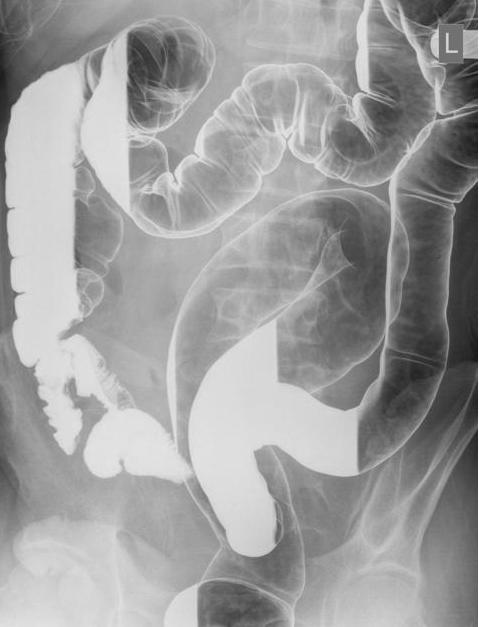

Image

radiologique de lavement baryte en double de contrast d'une

colite ulceree ( RCH )

Aspect granitee de la muqueuse au niveaux

du rectum et du colon gauche au cours une

rectocolite hemorragique . Image lavement baryte en

double de contrast du colon . |

Aspect de

granite de la muqueuse du colon descendant avec de perdre

de haustral d'une colite ulcereuse. Le colon sigmoide est en forme de

tubules et de micro rectum " lead pipe colon " .

Stenose serre en ficele de la jonction

colo-sigmoidienne et aspect microrectosigmoide en

tubule . Cancer du colon complicant d'une

rectocolite hemorragique . |

Stenose

polypoide sur un micro colon tubuleaire d'une cancer du

colon compliquant une colite ulceree (RCH) . |